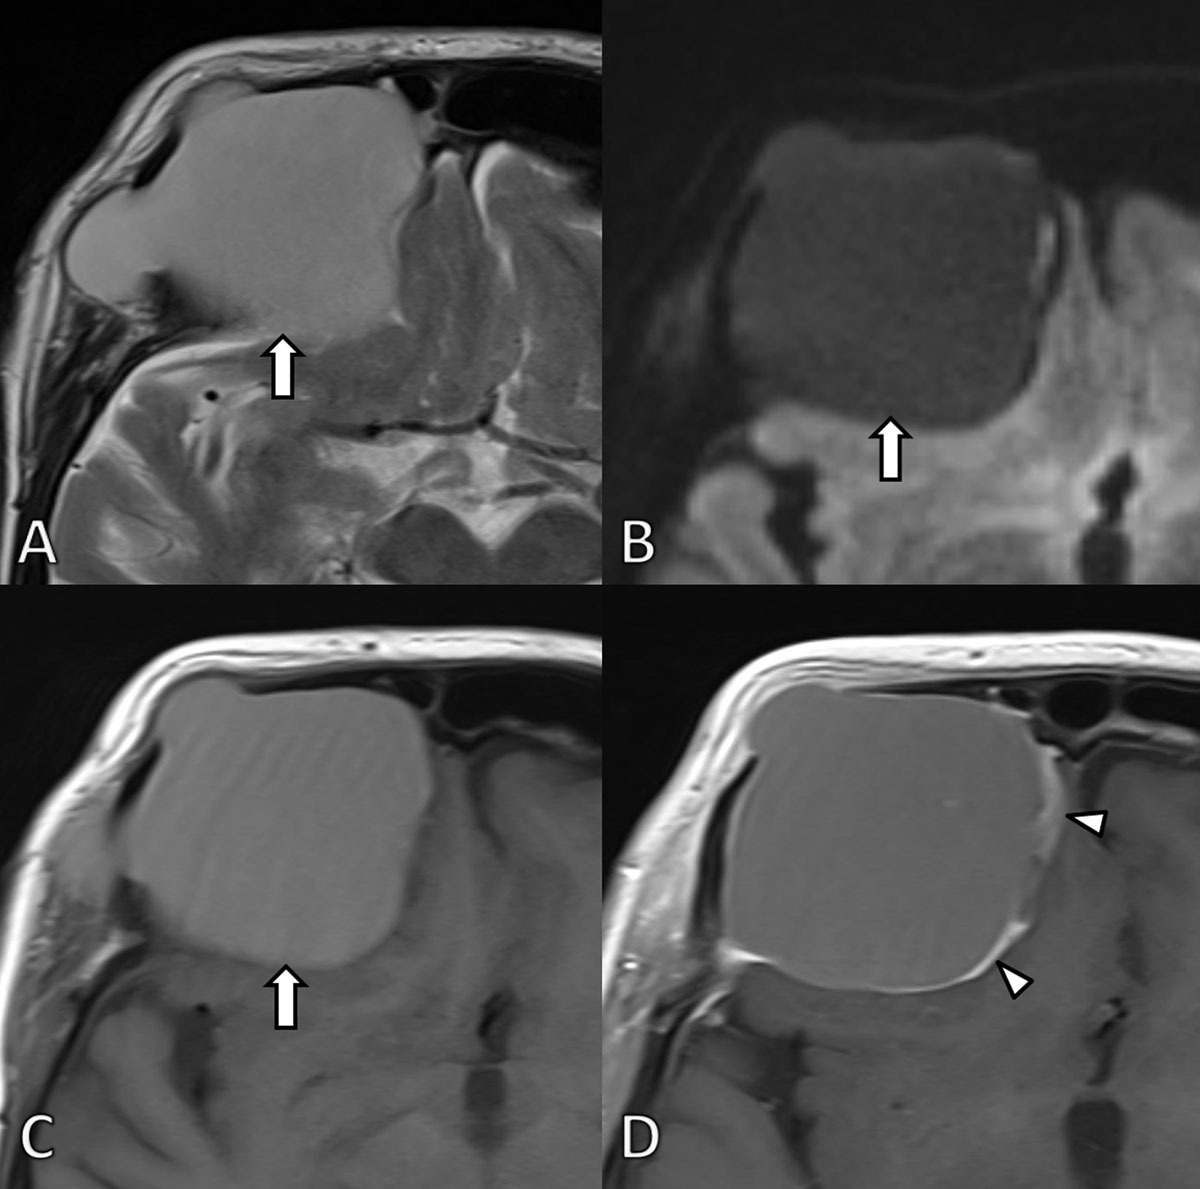

Subsequent MRI of the brain (Figure 2) depicted a well-defined expansile mass being slightly hyperintense on T1-weighted images (WI) and markedly hyperintense on T2-WI. A neurosurgical consult was planned but the patient did not show up. The patient was readmitted four years later because of recurrent falls and memory loss. Repeated CT (Figure 3) and MRI (Figure 4) demonstrated progressive expansion of the mass with increased destruction of the frontal bone. Based on the location at the frontal sinus and the imaging features, a presumptive diagnosis of a giant frontal mucocele was made, which was confirmed upon neurosurgical resection.

Figure 2

MRI at first admission. A. Axial T2-WI. B. Diffusion weighted image (b1000) and C. T1-WI before and D. after gadolinium contrast administration confirm the presence of a well-defined expansile mass (arrow) at the frontal bone. The signal is homogenously hyperintense on T2 and T1-WI images in keeping with high protein content. The lesion did not demonstrate restricted diffusion. After administration of gadolinium contrast the lesion shows subtle peripheral contrast enhancement (arrowheads). The lesion exerts mass effect on the frontal lobe.